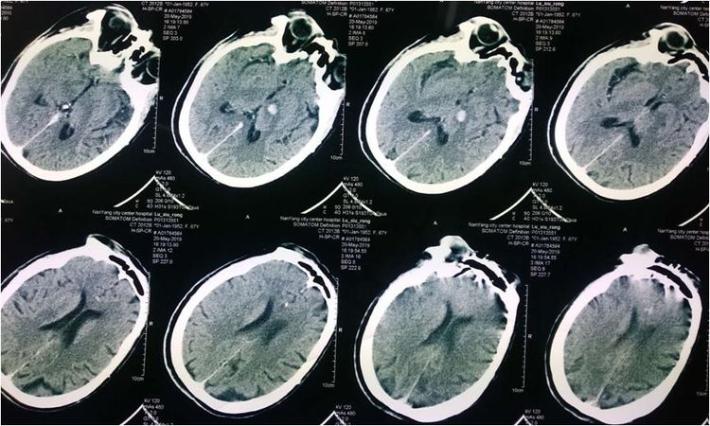

神经系统查体:神志清,精神差,饮水呛咳,双侧肢体肌力3级。NIHSS评分:11分。 于05.18 07:30(发病1小时)左右给予阿替普酶静脉溶栓治疗(具体不详),患者双侧肌力好转至4级,NIHSS评分改善至7分。 5月19日患者症状加重,出现意识水平下降, 神志昏睡,双侧肌力肌力2级,为求进一步诊治来我院。行头部CT提示:左侧丘脑出血。

复查头部CT未见出血加重。

术后复查头部CT:左侧丘脑血肿无扩大,未见造影剂渗漏。